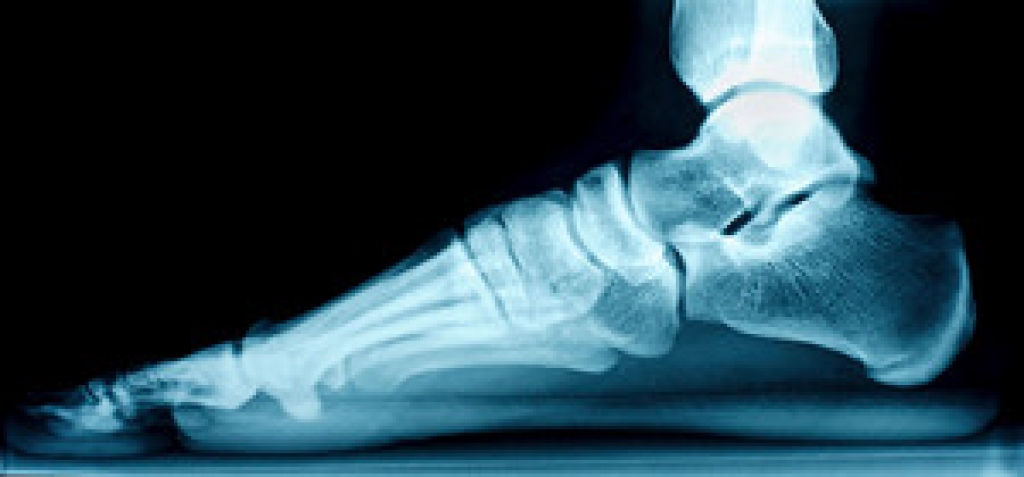

Lower limb and foot injuries are common in athletic children, partly due to the vulnerability of their growth plates. Growth plates are the developing areas of cartilage at the end of the long bones in the legs where bone growth takes place. These plates are weaker than nearby tendons and ligaments, making them more susceptible to injury. This is especially true when under the stress of repetitive physical activities in sports. Movements like running, jumping, and quick pivoting can place excessive strain on growth plates, leading to conditions such as Sever's disease, or heel pain. Ankle sprains are also common because ligaments in children tend to be more elastic than in adults. The biomechanics of growing children, such as variations in gait, muscle strength, and coordination during growth spurts, can further predispose them to these injuries as their bodies adapt to rapid physical changes. A podiatrist, or foot doctor, can treat these types of injuries common in active children. They may suggest treatments ranging from rest and elevation to custom orthotics that support proper alignment and reduce stress on the growth plates. Treatments vary depending on the injury. If your child is struggling with a lower limb or foot injury, it is suggested you consult with a podiatrist for targeted care.